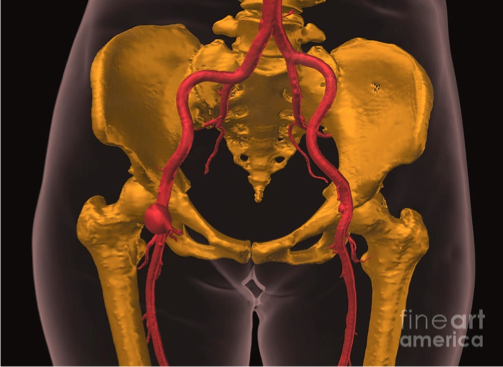

Aortic dissection

What does this refer to

Tear in the inner wall of the aorta (intima) causes blood to flow into the middle layer (media) and force the layers apart

Aortic dissection

What does this refer to

Etiology/Pathogenesis/Risk Factors Aortic Dissection

Stanford Typing System Aortic Dissection

What does this refer to

Most commonly in the aortic arch or L subclavian

Always include in differential of chest pain

Typically c/o severe sharp, “tearing” (ripping) sensation in the chest or back

Be suspicious of dissection in high risk patients c/o pain radiating to the back

Pain may migrate as the dissection extends

Stanford Type A-chest pain anteriorly—may hear new murmur in aortic area

Stanford Type B-may see pain between scapular areas/back pain.

Neck or jaw pain may occur with involvement of aortic arch

Pertinent Historical findings/clinical Sx Aortic Dissection

Peripheral extremity pulses may be decreased

Elevated BP in most cases (may see decreased BP)

Difference in pulse amplitude (strength)

Unequal BP in upper extremities (UE)

Aortic valve or ascending is affected new aortic regurgitation murmur